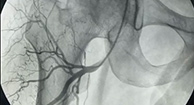

在千级层流无菌手术室内采用专利技术—可视血堵融通术,微创疏通股骨头堵塞的血管,恢复股骨头供血供氧,有效解除疼痛。

直观 血管融通前后动态对比 ↑↑↑

“可视血堵融通术”由孙伟主任为首的专家团队共同研发而成,已获得技术专利,该技术以“无孔不入、无孔也不入”的鲜明优势,疏通堵塞供血动脉,30分钟打通股骨头血运,药物直达病灶,避免置换,目前该项技术已得到国医大师等业内诸多专家学者的肯定,且获名家访谈之《医生来了》栏目认可。